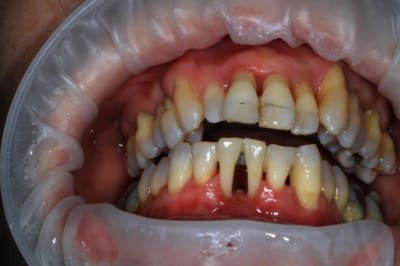

un peu de grain à moudre, toutes les critiques sont les bienvenues...

1ere séance,"nettoyage...", et après réflexion, plutôt que le nettoyage par le vide, attelle de contention pour le bloc antérieur mandibulaire, suppression de quelques contact très parasite sur les pm et canines, et réduction des incisives mandibulaire puis maxillaire... consignes de brossages / bain de bouche avec .... l'érythritol afin de ne pas mourir idiot... on verra ce que ça donne dans un cas relativement perdu d'avance.... merci Algi... enfin peut être : -))